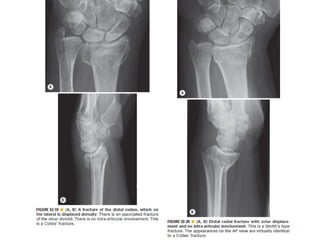

Skeletal trauma was presented by Dr Laith Fadhel with reference to Grainger's Diagnostic Radiology textbook. The presentation covered skeletal trauma as assessed through diagnostic radiology techniques. Key findings and treatments for skeletal injuries were likely discussed.